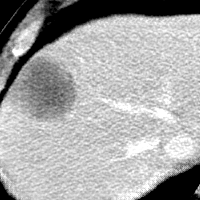

Refer to caption

CT

Zoomed

MRI

Target\mathrm{Target}

StolenEPD{\mathrm{Stolen}}^{\mathrm{D}}_{\mathrm{EP}}

StolenEPD1{\mathrm{Stolen}}^{\mathrm{D1}}_{\mathrm{EP}}

StolenITD{\mathrm{Stolen}}^{\mathrm{D}}_{\mathrm{IT}}

StolenITD1{\mathrm{Stolen}}^{\mathrm{D1}}_{\mathrm{IT}}

Figure 7: Lossy image reconstructions on CT (row 1, 2) and MRI (row 3, 4) images, where the row 2, 4 provide a zoomed-in view of the bounding box region of the row 1, 3. The leftmost column represents the target images, while the subsequent four columns show the stolen images reconstructed by the decoder D or D1 in two scenarios.

A visual comparison between target and stolen images is available in Fig. 7. We observe that the stolen images from IT Scenario closely resemble the input ones, particularly in the tumor regions, whereas stolen images from EP Scenario exhibit blurring artifacts in finer details. In both cases, the stolen images reconstructed by D1D1 demonstrate a comparable quality to those reconstructed by DD, thus further confirming the effectiveness of the reduced decoder D1D1.